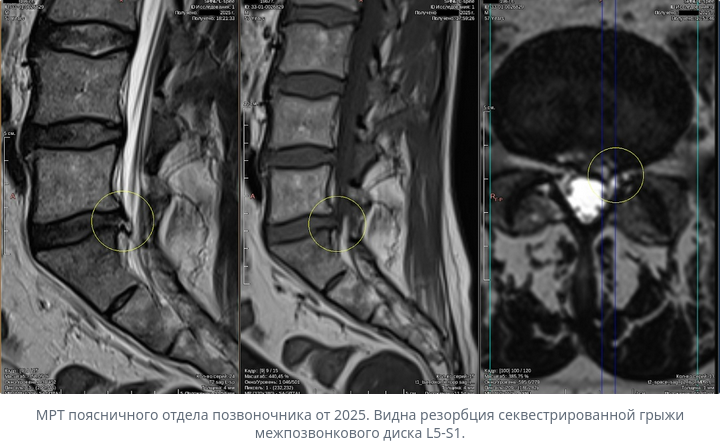

Хорошая новость: грыжа межпозвоночного диска часто сама рассасывается без операции. Организм воспринимает выпячивание диска как инородное тело и постепенно его разрушает и выводит. Это называется резорбция (от слова «рассасывание»).

Такое рассасывание происходит у 70–77% пациентов, которые придерживаются консервативного лечения (без операции). Для крупных грыж, которые отделились и выступают в спинномозговой канал, вероятность ещё выше — до 96%.

Сколько времени занимает рассасывание

- Обычно основное рассасывание происходит в первые 6 месяцев консервативного лечения

- Полное исчезновение может занять 6–12 месяцев, иногда дольше

Важный момент: Даже если грыжа не полностью исчезает, её уменьшение часто приводит к значительному улучшению симптомов.